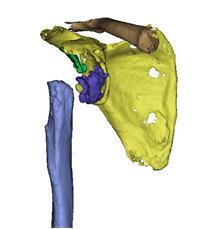

韵向东主任考虑到患者年龄较轻,生活质量要求较高,为了最大限度地恢复保留患者的肩关节功能,决定结合与国际接轨的3D打印数字化假体最新技术,个性化定制了反肩关节假体,降低了因关节畸形及缺损,周围肩袖缺失等增加的手术难度及风险,同时也大大缩短了手术的时间,让反肩置换更加精准,患者满意度大幅度提高!

术前个性化定制3D打印-反肩关节置换假体,结合病情设计修补重建及定位点